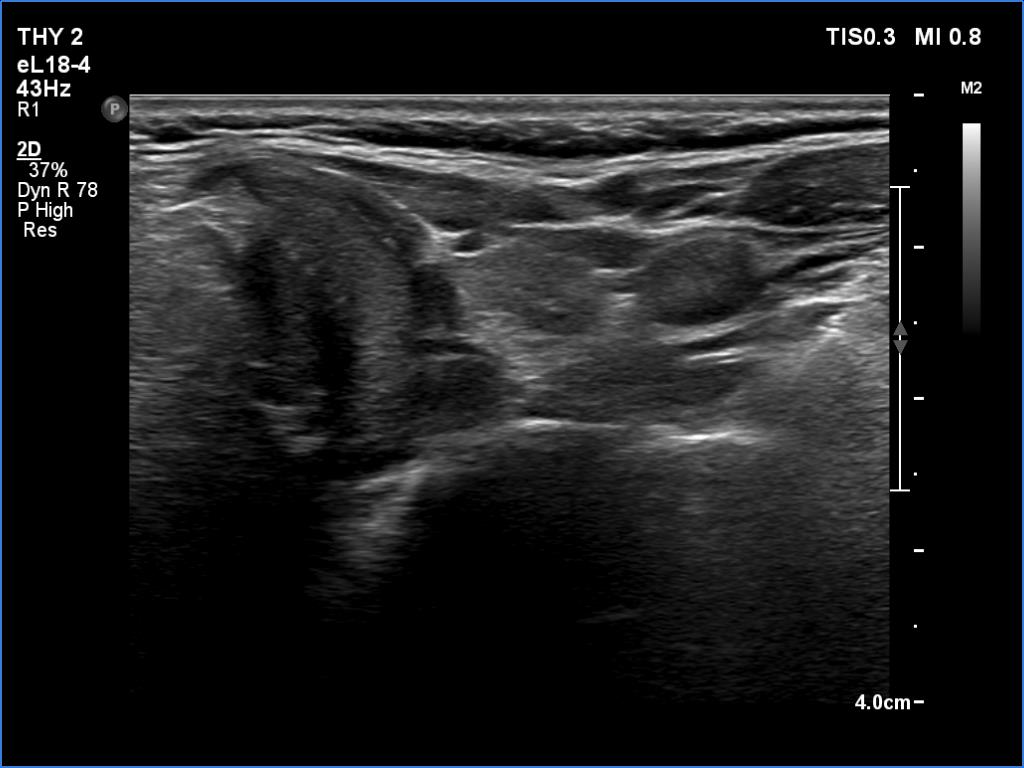

Lymphocytic thyroiditis - case 1441

Right lobe

Left lobe

Focal form of lymphocytic thyroiditis is presented. The thyroid has numerous discrete, hypoechoic lesions which correspond to more active foci of thyroiditis. The interpretation of the relatively large ventral hypoechoic area in the left lobe (right upper image can cause problem), however, longitudinal scan decides the issue: this field cannot be a pathological nodule.